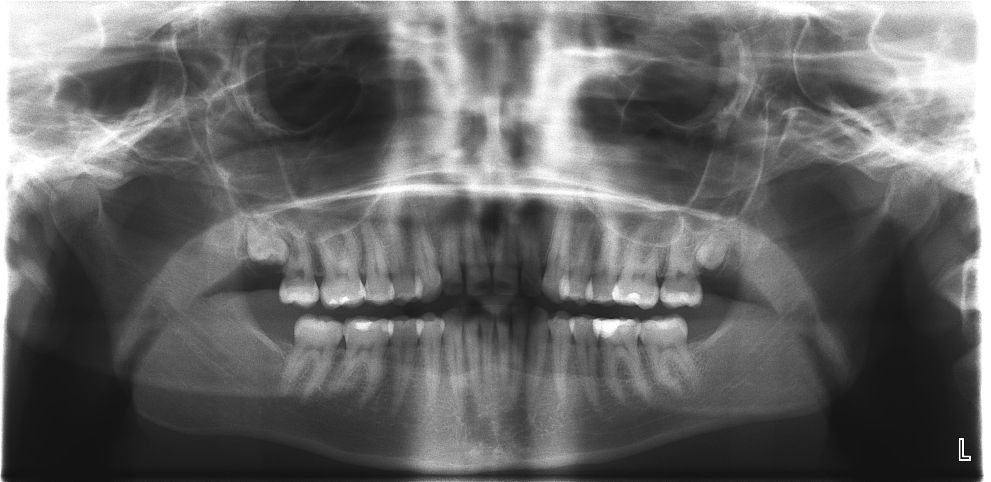

Рентгеновский снимок, который захватывает область от одного височно-нижнечелюстного сустава до другого, при этом на пленке имеется изображение всех зубов, называется панорамным. В качестве примера подобный дентальный рентгеновский снимок приведен на рисунке ниже.

Данный снимок позволяет визуализировать состояние костных структур верхней и нижней челюсти и зубов.

Что позволяет диагностировать панорамный снимок? Спектр возможностей этого вида дентального рентген-исследования включает:

- оценку состояния здоровья всех зубов, например, при первом приеме у стоматолога;

- оценку качества выполнения ранее проведенных работ в ротовой полости;

- выявление скрытых кариозных полостей;

- выявление воспалительных очагов в области зубов и обеих челюстей (киста зуба, гранулемы, остеомиелит);

- обнаружение опухолей этой области, как доброкачественных, так и злокачественных;

- обнаружение переломов и трещин зубов и челюстей;

- оценку тяжести и стадии пародонтита, пародонтоза.